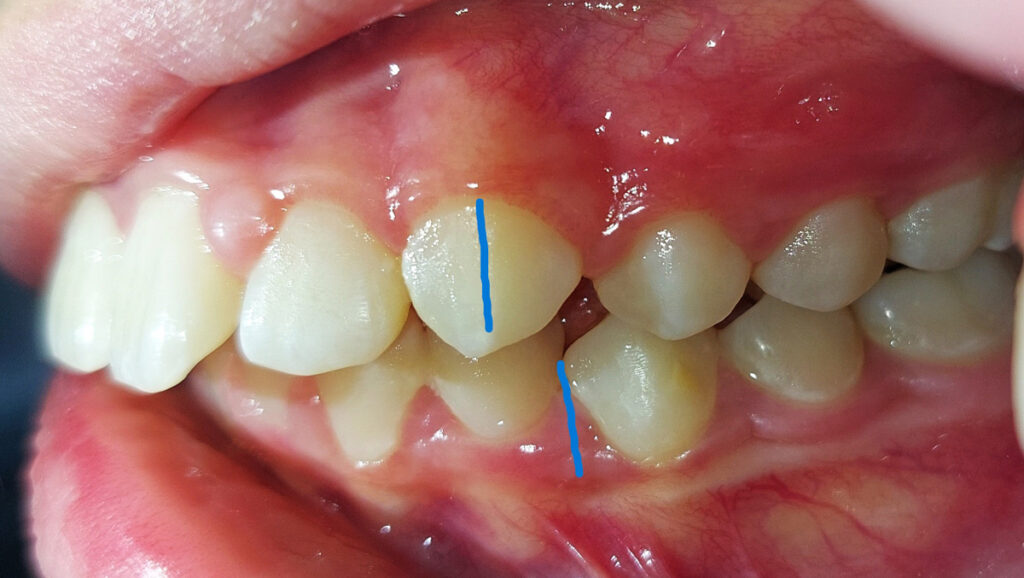

A Class II malocclusion is characterized by an upper jaw that is too far forward relative to the lower jaw, or lower teeth that are too far back relative to the upper teeth.

In conclusion, this type of malocclusion can have a dental cause, a skeletal cause, or both. Frequently, the lower teeth then come into contact with the palate rather than the upper teeth during chewing.